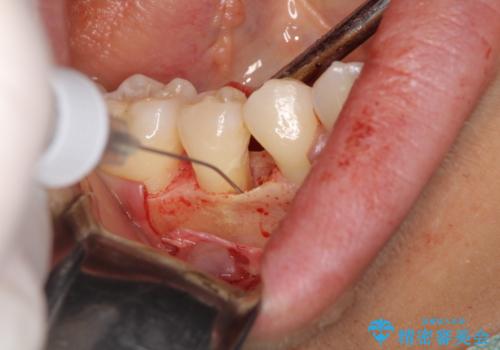

歯肉移植をを行うこととなり、今回は一番歯茎が下がっている右上2番を中心に、手術をすることとなりました。

歯肉移植の目的は下がってしまった歯茎を回復させることと、歯肉の厚みを増やし、今後歯肉退縮の予防をすることになります。

今回の手術した部位に関しては、今後歯茎が下がっていく可能性はかなり少なくなったと言えます。